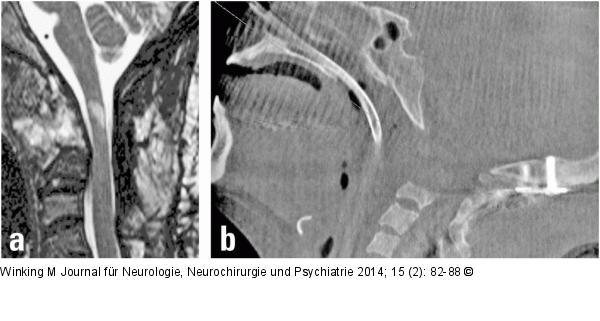

Abbildung 10a-b: Rheumatische Wirbelsäule (a) Sagittales T2-MRT nach okzipito-zervikaler Stabilisierung und transoraler Densresektion. Im Myelon erkennbare strukturelle Schädigung durch die ursprüngliche Kompression. (b) Intraoperative 3-D-Darstellung des kranio-zervikalen Überganges nach transoraler Densresektion. |

(a) Sagittales T2-MRT nach okzipito-zervikaler Stabilisierung und transoraler Densresektion. Im Myelon erkennbare strukturelle Schädigung durch die ursprüngliche Kompression. (b) Intraoperative 3-D-Darstellung des kranio-zervikalen Überganges nach transoraler Densresektion. |